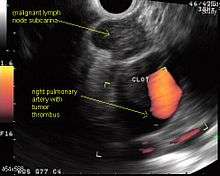

Endoscopic ultrasound (EUS) is an endoscopic technique where a miniaturized ultrasound probe is passed though the mouth into the upper gastrointestinal tract to investigate organs and structures close to the esophagus, stomach, or duodenum, such as the lung. In 1993, Wiersema published the first description of EUS to diagnose and stage lung cancer,[27] done by advancing a fine needle through the esophagus into adjacent lymph nodes. Numerous subsequent studies have shown this general methodology to be effective, very safe, minimally invasive, and very well tolerated. Given these advantages, many authorities think that EUS together with endobronchial ultrasound (EBUS) enhances lung cancer diagnosis and staging.[28]

Endoscopic ultrasound (EUS)

A metaanalysis published in 2007, based on 1,201 cancers in 18 high-quality clinical trials carefully selected by predefined criteria from the literature, systematically examined the performance of EUS-guided FNA in NSCLC staging. Two scenarios were considered: the setting of enlarged lymph nodes on CT (suggestive but not diagnostic of cancer), and the obverse scenario of an absence of lymph node enlargement on CT (suggestive but not diagnostic of no cancer).[24] Overall, in both settings, minor complications were reported in 0.8% of procedures; no major complications were recorded. EUS-FNA in enlarged discrete mediastinal lymph nodes had an excellent pooled sensitivity (8 studies) of 90% (95% CI, 84 to 94%) and specificity of 97% (95% CI, 95 to 98%). EUS-FNA in the setting of no enlarged mediastinal lymph nodes on CT had a pooled sensitivity (4 studies) of 58% (95% CI, 39 to 75%) and specificity of 98% (95% CI, 96 to 99%). Although this sensitivity (58% in CT-negative disease) might on first consideration seem disappointing, if EUS is performed as a staging test it can help avoid more invasive staging procedures, or surgery, if positive (for the presence of cancer). In other words, an EUS that has a positive result (shows cancer) will avoid further needless surgery, whereas a result not showing cancer may be false-negative, and probably requires an excisional biopsy technique for confirmation, such as VATS or mediastinoscopy.

EUS can reliably reach the lymph node stations 5, 7, 8 and 9. In the superior mediastinum the trachea is somewhat to the right of the esophagus which makes it often possible to reach left-sided area 2 and 4 lymph nodes and, less often, right sided paratracheal lymph nodes.[29] In general, EUS is most appropriate for evaluation of the posterior inferior mediastinum while mediastinoscopy or EBUS are best for the anterior superior mediastinum. The feasibility of EUS-FNA of aorto-pulmonary window (subaortic) lymph nodes (station 5) is a major advantage of EUS. Evaluation of this station has traditionally required a paramedian mediastinotomy (Chamberlain procedure). EUS can easily sample celiac lymph nodes, which cannot be reached by the other mediastinal staging methods. In one recent study an unexpectedly high incidence of celiac lymph node metastasis (11%) was noted.[30] EUS can also be used to biopsy potential left adrenal metastases, whereas the right adrenal gland is mostly inaccessible.[31]

Endobronchial ultrasound (EBUS)

As mentioned in the table, EUS cannot reliably access right sided paratracheal lymph node stations 2R and 4R and may not be optimal for the left sided paratracheal lymph node stations either. An adaptation of the endoscopic ultrasound scope originally designed for the gastrointestinal tract is known as endobronchial ultrasound (EBUS). The instrument is inserted into the trachea rather than the esophagus. There are two types of EBUS bronchoscopes available: radial catheter probe and convex probe EBUS (CP-EBUS),[33] but only the latter concerns us here. Early experience with mediastinal staging by CP-EBUS appears very promising with sensitivities ranging from 92 to 96 percent in 4 series comprising 70 to 502 patients.[34][35][36][37]